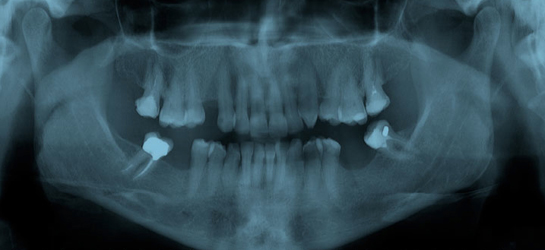

QUESTION: I am an associate currently working as an independent contractor for an office where they do not provide any compensation for the X-rays taken on patients. The office manager says that the reason is because the assistant takes the X-rays and he/she gets the credit for completing that action while the doctor gets the credit of the exam. By definition of the exam, it includes the use of any aids, including images present.

My argument is that I am responsible for the interpretation of the images taken, and my license is what is being used to claim reimbursement.